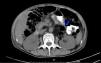

A CT scan of the abdomen revealed a heterogeneous formation consisting predominantly of fat content, with its epicentre in the retroperitoneal region, associated with diffuse densification of the abdominal mesenteric fat and the thickening of the small-bowel intestinal loop wall, whose differential diagnosis included a tumour of lipomatous lineage (Fig. 1).